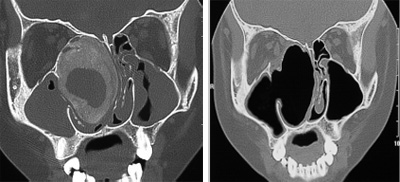

鼻咽纤维血管瘤

骨化纤维瘤

斜坡脊索瘤

图8 鼻内镜外科技术的延伸:鼻颅底、鼻眼相关精准手术